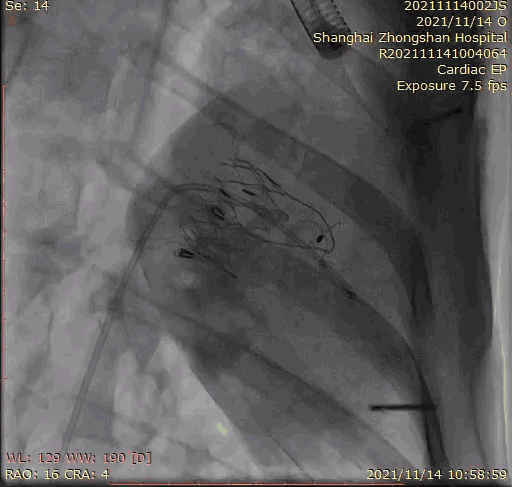

本次臨床前研究經(jīng)右側(cè)頸靜脈置入LuX-Valve Plus輸送系統(tǒng)可調(diào)彎鞘管,在DSA及超聲引導(dǎo)下將人工三尖瓣瓣膜植入到原有三尖瓣位置,利用獨(dú)特的錨定技術(shù)將人工瓣膜支架可靠固定在預(yù)定的位置。

Lux-Valve是全球第一款具有我國(guó)完全自主知識(shí)產(chǎn)權(quán)的經(jīng)導(dǎo)管介入三尖瓣置換系統(tǒng),利用前瓣夾持及室間隔錨定的復(fù)合方式進(jìn)行瓣膜裝置的固定,不依賴(lài)瓣環(huán)徑向支撐力,同時(shí)采用自適應(yīng)復(fù)合裙邊材料,有效的貼合密封柔軟的三尖瓣瓣環(huán),針對(duì)于三尖瓣返流的患者有優(yōu)異的療效。Lux-Valve Plus采用全新的經(jīng)血管輸送系統(tǒng),經(jīng)頸靜脈入路創(chuàng)傷更小,可以進(jìn)一步降低手術(shù)風(fēng)險(xiǎn)。相信在后期正式臨床研究開(kāi)展中,Lux-Valve Plus必定會(huì)為更多的三尖瓣反流患者帶來(lái)福音。